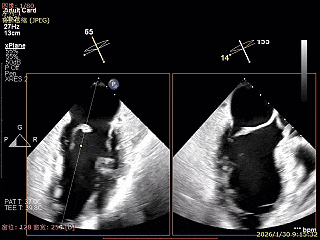

X-Plane切面切1区未见明显异常

1区上Color,未见反流来源

X-Plane切面切2区可见前叶Flail

2区上Color,可见反流来源

X-Plane切面切3区可见前叶脱垂

3区上Color,可见反流来源